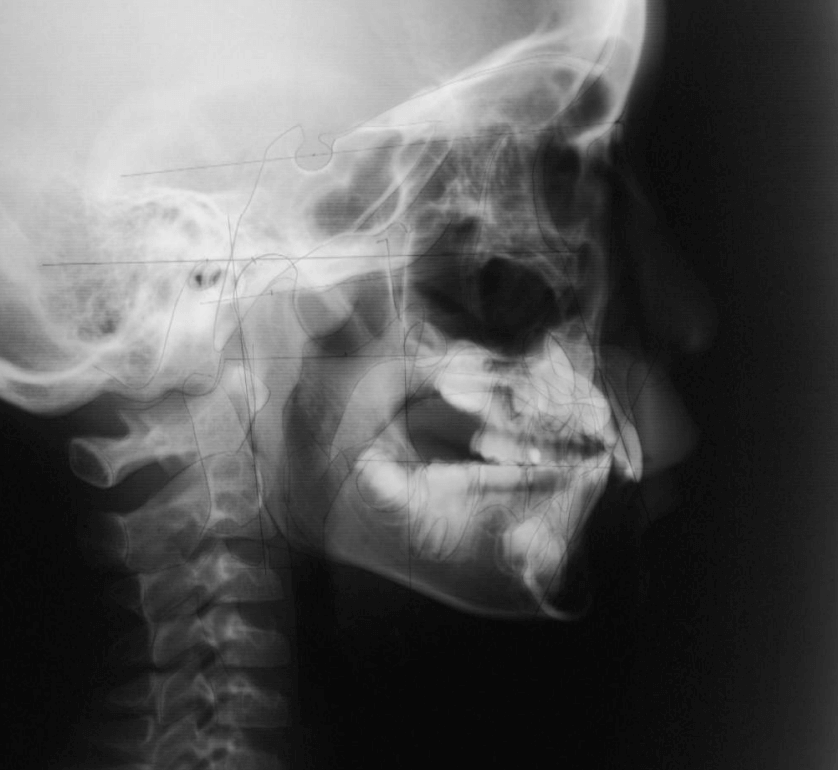

| 年齢・性別 | 11歳1ヶ月の女性 |

|---|---|

| 主訴 | 口元の突出感と歯並びが気になり、将来的な咬合状態を整える目的で来院された患者様です。 |

| 治療期間・回数 | 2年6ヶ月・25回 |

| 費用 | 720,000円 |